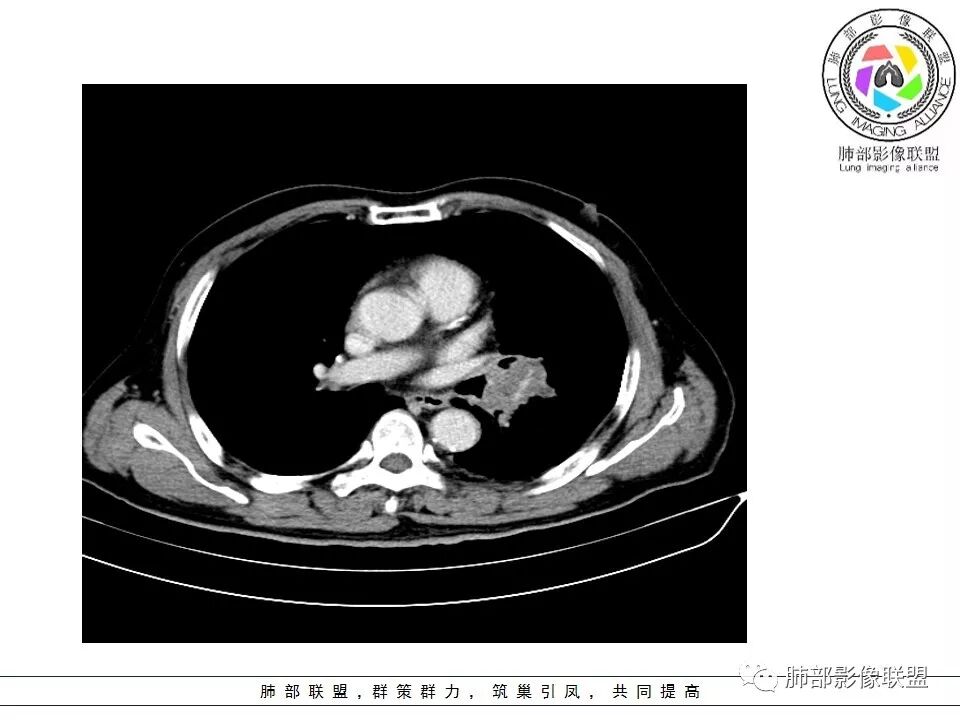

恶性没问题吧  ,哪位老师标示一下病灶

那些是淋巴结?哪是主病灶?

支气管如何?肺动脉?肺静脉?

南边:我发一个图

南边:这病灶与支气管啥关系啊?

南边:与肺静脉啥关系?这样追下去是不是很恶啊

南边:病灶分为两大块,外围囊实性大肿块,支气管关系不密切,内带多发淋巴结,侵犯支气管、肺血管,恶性没问题,按理间叶为主,或不典型的癌,这不是一个中央型的肺癌,是外朝内进展的,奇怪的是边界这么清楚光滑,一般癌肉瘤、肉瘤类多,其次才是癌,远端也没有阻塞,大方向是这样,恶性,间叶来源?或者混合,恶性程度较高,鉴别就是结核,因为结核是妖

1.左肺下叶近肺门区肿块,肿块外围大,内带小,提示外围向中央生长,符合周围型SCLC沿支气管方向生长。

2.病灶边缘光滑,未见明显分叶、毛刺,符合神经内分泌癌、癌肉瘤及间叶来源肿瘤。

3.病灶内密度偏低,穿行血管未见明显异常,轻度不均匀强化,为乏血供病灶。病灶内可疑坏死区,未见空洞;乏血供符合SCLC,但坏死区不符合。

4.病灶区支气管以受压推移为主,管腔不规则,腔内通而不畅,提示病灶粘膜下为主,符合SCLC迁徙蔓延或间叶来源肿瘤。

5.病灶内有血管走行,血管局部受压,但是强化考虑为乏血供,提示病灶内肺动脉并不是供血血管,只是病灶侵袭性强把血管包埋而已,为血管包埋征;血流面光滑,血管包埋符合SCLC。

6.左肺门淋巴结肿大,与病灶局部融合分界不清,呈冰冻肺门;而纵隔内未见肿大淋巴结,冰冻肺门符合SCLC,但是病灶主体那么大,纵隔内没有明显肿大淋巴结,不是很符合SCLC娘小崽大的特点。

7.未见明显阻塞性炎症及阻塞性肺不张,更加提示病灶从外围向中央侵犯,符合SCLC罕见阻塞性肺不张。